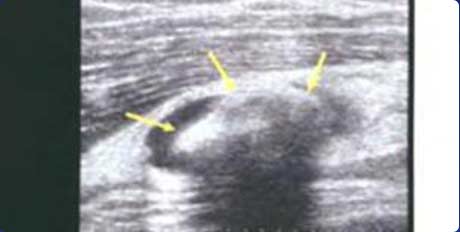

回声伴声影

膝关节髌上囊扩张积液,可见团状强回声,并伴声影

高回声团

关节横纵扫描图像,尿酸盐沉积形成略高回声团块-痛风石